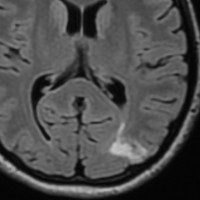

限局性のびまん性星細胞腫

無症状で発見された若年成人のびまん性星細胞腫,一つの脳回に限局するタイプでsingle gyrus gliomaといいます